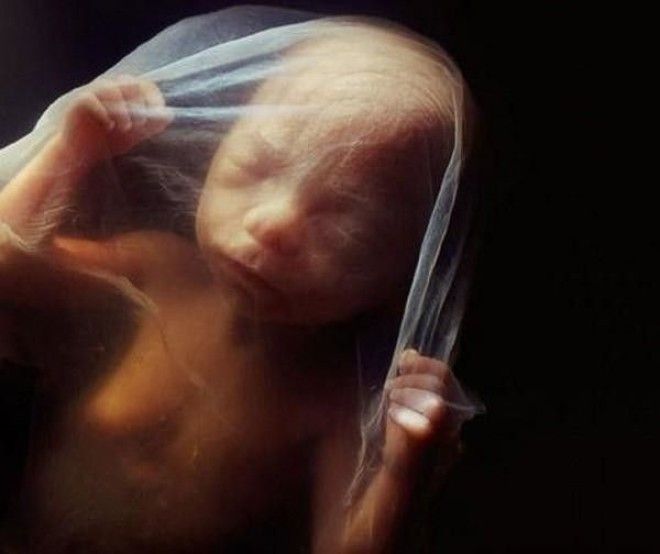

16 недель

.

Сквозь тонкую кожу видна сеть кровеносных сосудов